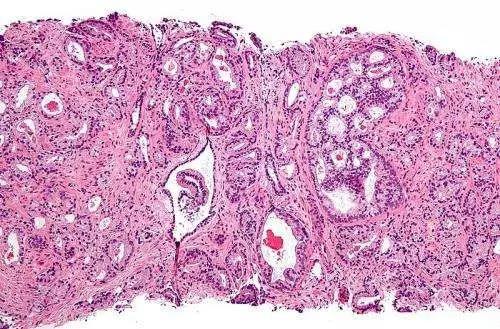

结直肠癌,一种可以保持沉默的癌症,结直肠癌早期可以没有任何症状出现,却是美国癌症有关死亡的第三大原因。3月份是结直肠癌月,您对于结直肠癌有足够的认识吗?

结直肠癌早期没有任何症状,一经发现多数已为晚期。但是,筛查可以帮助早期发现癌症,可能涉及粪便检查、结肠镜检查或其他手术。无风险的普通人在50岁时也要开始进行结直肠癌筛查,但具有较高风险因素的人群,如克隆氏病史、炎症性肠病或有某些遗传标记的,应该更早开始筛查。尽管结直肠癌每年会导致大约5万名美国人死亡,但您依旧可以降低患癌风险。增加体力活动、限制酒精摄入量和避免吸烟已被证明完全可以降低结直肠癌风险。

结肠直肠癌是可以高度治疗的,并且越早发现,存活机会越大。所以,不要忽视筛查。这个结直肠癌月,您是不是该做点什么了?